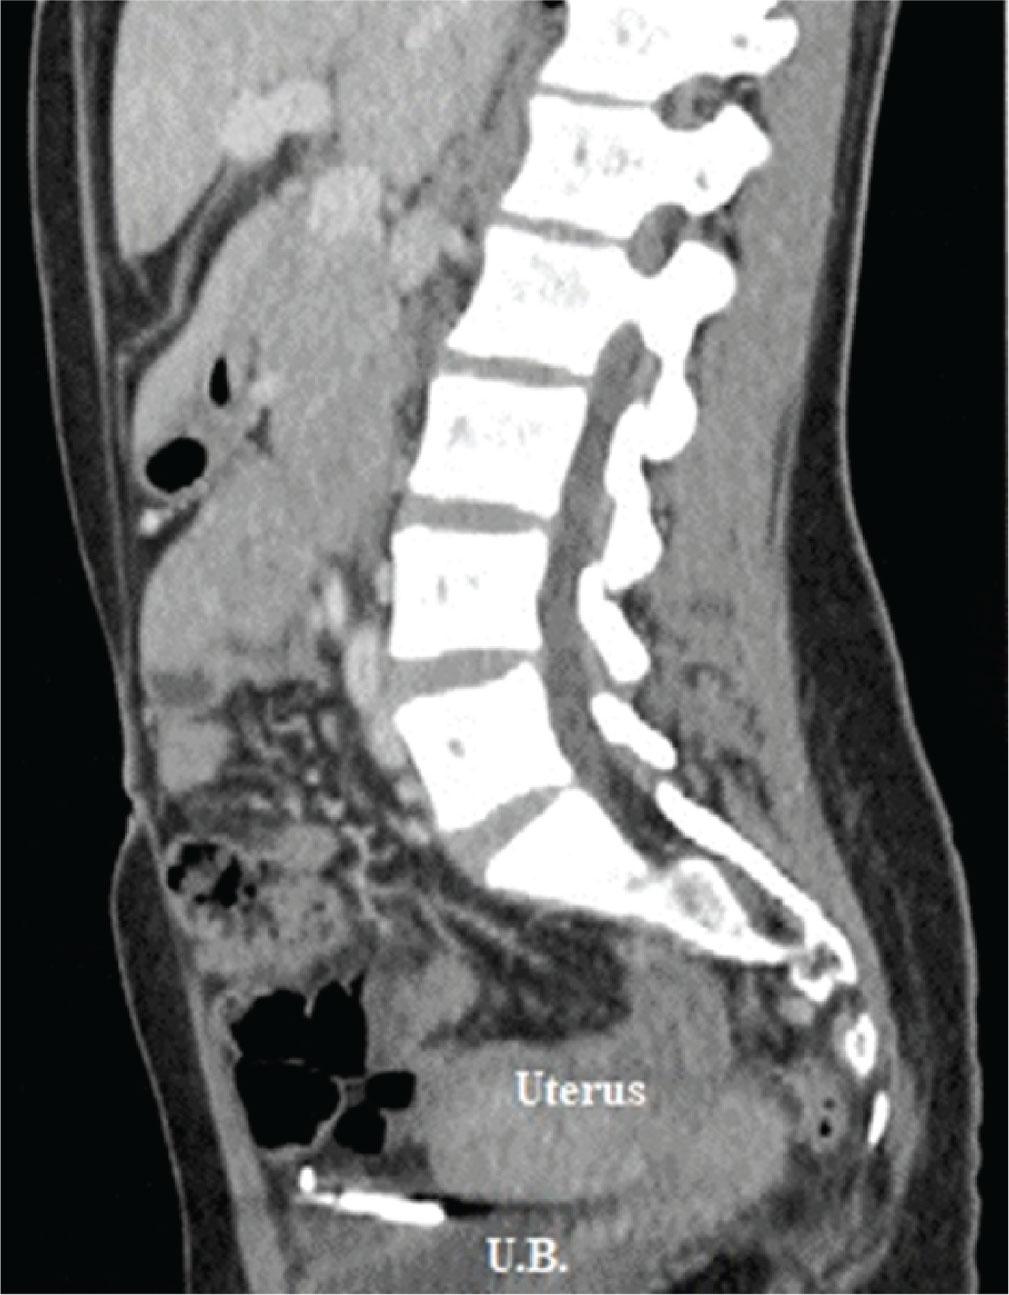

After the exclusion of pregnancy with human chorionic gonadotropin measurement, both a combined abdominal and pelvic X-ray and a departmental transvaginal ultrasound suggested an extrauterine location of the device. Computed tomography with contrast demonstrated the IUD to be located intraperitoneally between the urinary bladder and uterus (Figure 1).

Computed tomography confirms an IUD to be extrauterine in location, between the urinary bladder and uterus.